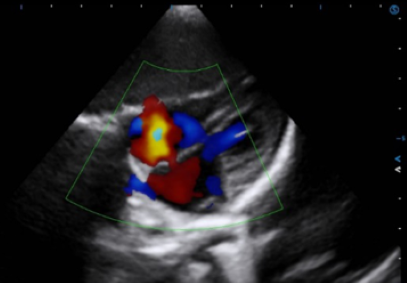

Auto EF facilitates cardiac systolic function assessment by automatically identifying and tracking the endocardium, and accurately calculating the LV EF within seconds.

Auto SG empowers objective evaluation of LV systolic function and myocardial deformation through quantitative results in a bull’s-eye plot.

TDI QA quantitatively analyzes the myocardial motion with multiple sampling points for convenient comparison and evaluation.

Stress Echo analyzes myocardial motion at rest and under stress to help evaluate how coronary arteries respond to the stress.